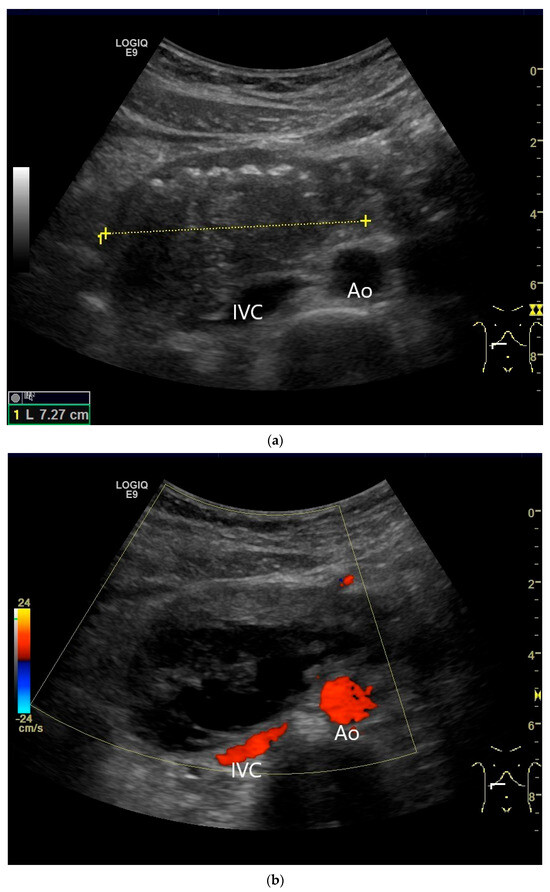

Figure 20.

Crohn’s disease under anti-inflammatory therapy, anastomosis after ileocecal resection. Hypoechoic wall thickening of the neoterminal ileum without definable stratification (a). Numerous vascular reflexes are visible in color Doppler (b), indicating ongoing inflammation.

Figure 21.

Duodenal wall hematoma after gastroscopy with forceps biopsy under dual antiplatelet therapy. Clinically, there was pain and lumen obstruction. Evident focal hypoechoic wall thickening (between the markers) with lumen obstruction (a), for which there was no correlation in the previous gastroscopy. No evidence of macro vessels in CDI (b). In CEUS, the mass is smoothly defined and completely non-enhanced (c). IVC—inferior caval vein, Ao—aorta.

Figure 22.

Jejunal wall hematoma with a Quick ratio <5%. Smoothly defined, distinct wall thickening and lumen obstruction. The wall stratification is indistinct, slightly hyperechoic, and clearly blurred and unfocused (a). The Kerckring folds are thickened and also very blurred (b).